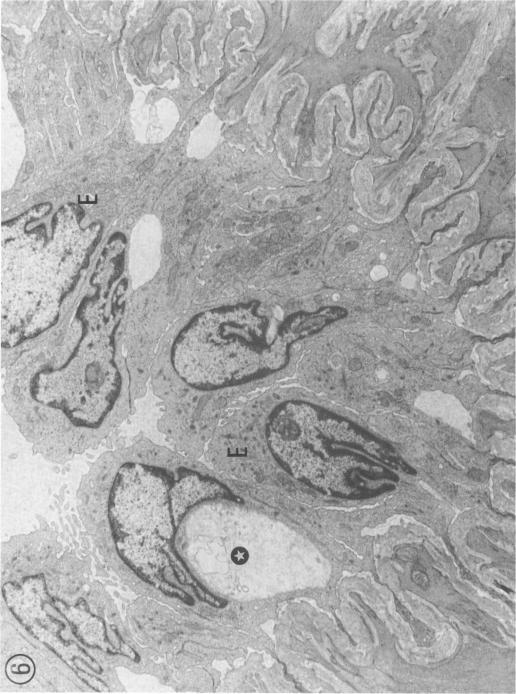

The histopathology of rat lung has been studied after an acute exposure to perfluoroisobutylene (PFIB) at a concentration of 638 mg/m3 (78 p.p.m.) for 1.5 min giving a Ct = 957 mg min/m3 for the first 24 h following exposure. Within 5 min of exposure changes to the bronchioles and peribronchial alveoli were observed which took the form of alterations to cilial structure, increased pinocytosis and electron lucency, with occasional vesicle formation of type I alveolar epithelial cells. Intercellular leakage with minimal fluid accumulation in the alveolar spaces was also seen. The very rapid action of PFIB strongly suggests a direct action by the compound. There then followed the gradual development of pulmonary oedema which was visible histologically 2-3 h post exposure with deaths occurring from 7 h onwards. Animals sacrificed at 24 h post exposure showed evidence of widespread pulmonary oedema and alveolar interstitial infiltration by lympho-mononuclear cells and macrophages.